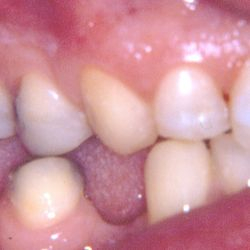

Ο κάτω γομφίος σε αυτή την νεαρή ασθενή έχει απονευρωθεί.

Για να εξασφαλίσουμε την καλή πρόγνωση του δοντιού και ταυτόχρονα την προστασία του από πιθανό κάταγμα, αποφασίστηκε η τοποθέτηση ενός επενθέτου εργαστηριακής σύνθετης ρητίνης.

Η διαδικασία ολοκληρώθηκε σε 2 ραντεβού, ενώ ο τροχισμός του δοντιού διατηρήθηκε στο ελάχιστο δυνατό.

Η εναλλακτική λύση θα ήταν να τροχιστεί εντελώς το δόντι και να τοποθετηθεί μια στεφάνη, οδηγώντας όμως έτσι σε αφαίρεση μεγάλης ποσότητας οδοντικής ουσίας.